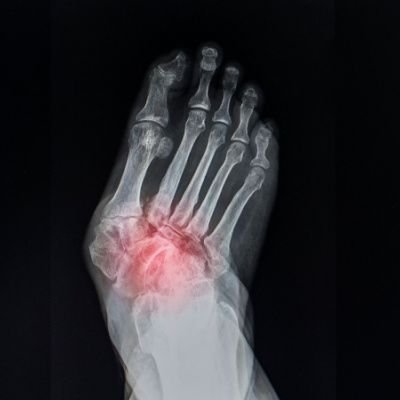

Imaging Studies

X-rays, magnetic resonance imaging (MRI), or computed tomography (CT) scans may be ordered to visualize the bones and joints. Imaging studies provide detailed insights into the extent of degeneration and aid in formulating an appropriate treatment plan.